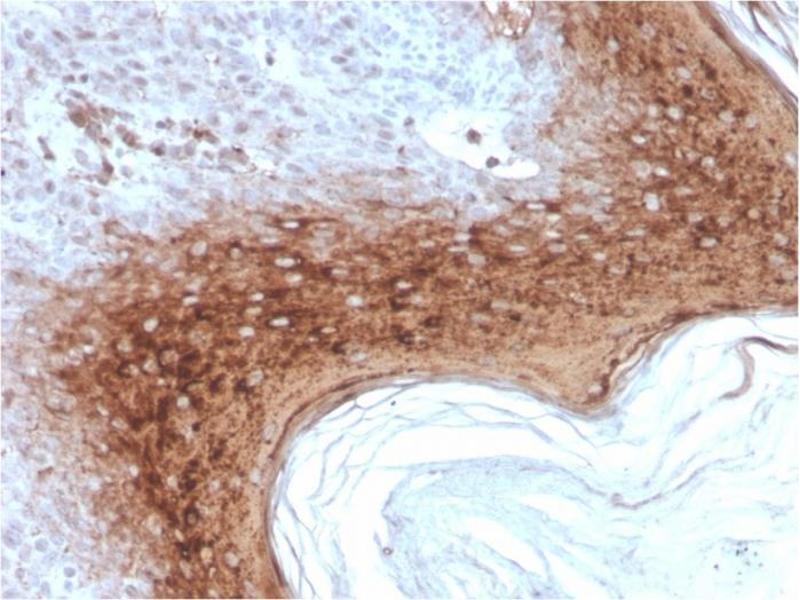

It recognizes a protein of 66 kDa-170 kDa, identified as involucrin. In Western blotting of cultured human keratinocytes, this MAb reacts with a 120 kDa protein. It stains the involucrin in a variety of sizes: 170 kDa in MCF-7 cells, a doublet of ~115 kDa and 150 kDa in gorilla and owl monkey, 66 kDa in dog, and a doublet of 105 kDa in pig. Its epitope maps between codon 421-568 of human involucrin. Involucrin is expressed in a range of stratified squamous epithelia, including the cornea, which lacks a distinct cornified layer. In normal epidermis, it is first expressed in the upper spinous layers, and in keratinocyte cultures, all cells that have left the basal layer express it. Involucrin expression is altered in pathological conditions: in psoriasis and other benign epidermal hyperplasias, involucrin expression begins closer to the basal layer than normal, expression is abnormal in squamous cell carcinomas and premalignant lesions, and is reduced in severe dysplasias of the larynx and cervix.

Positive Control: MCF-7 cells. Localized to upper spinous and granular layers in normal skin.